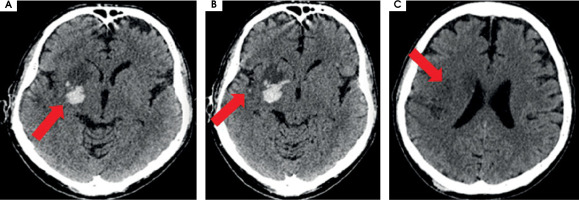

After MT the blood flow in the artery was returned with TICI 3 (Figure II). The day after the MT, control CT showed haemorrhagic foci (Figure III). The patient returned to the ICCU three days later. His neurological status was the same as before the MT of RMCA. In repeated CTs of the brain, haemorrhagic foci were still present (Figure IVA). In the following days of hospitalization, the resolution of haemorrhagic and evolution of ischemic cerebral lesions were observed (Figure IVB).

Figure III

Scans from control computed tomography of the brain performed the day after the procedure of thrombectomy. A) On the right side of the brain, in deep structures, hyperdense haemorrhagic foci are seen, with the greatest one 20 × 21 × 15 mm and a smaller satellite. B) Surrounding the M1/M2 segment of right middle cerebral artery, probably minor subarchnoid haemorrhage in the lateral sulcus on the right side is present. C) Acute ischemic lesions located cortico-subcortically in the right hemisphere, including part of the frontal, occipital, and temporal lobe and also thalamus, the islet, caudate nucleus, mass effect is present as a narrowed frontal horn of the right ventricle and a narrowed sulcus above the area of stroke